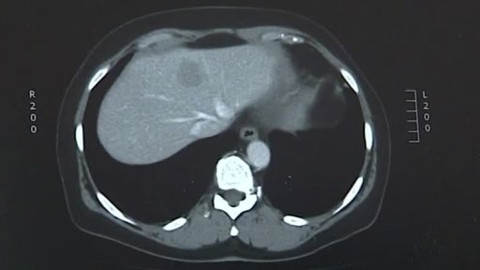

Každý rok je jich 350. Dětí a dospívajících, kteří onemocní leukémií nebo mají jiné typy nádorů. Ještě před půlstoletím by podobná diagnóza znamenala téměř jistou smrt, teď už doktoři dokážou zachránit 83 % malých pacientů. Bez akademických studií, které ženou medicínu v oblasti dětské onkologie dál, by ale děti s podobnou diagnózou neměly šanci ani dnes.

Počet nových případů rakoviny kůže za posledních 40 let narostl šestkrát. A nemoc je o to zákeřnější, že se z původního místa rychle umí přesunout jinam. Za nárůst nemocných může obliba opalování, řídnutí ozónové vrstvy i dědičnost. Proč se stále tolik Čechů rakoviny nebojí?